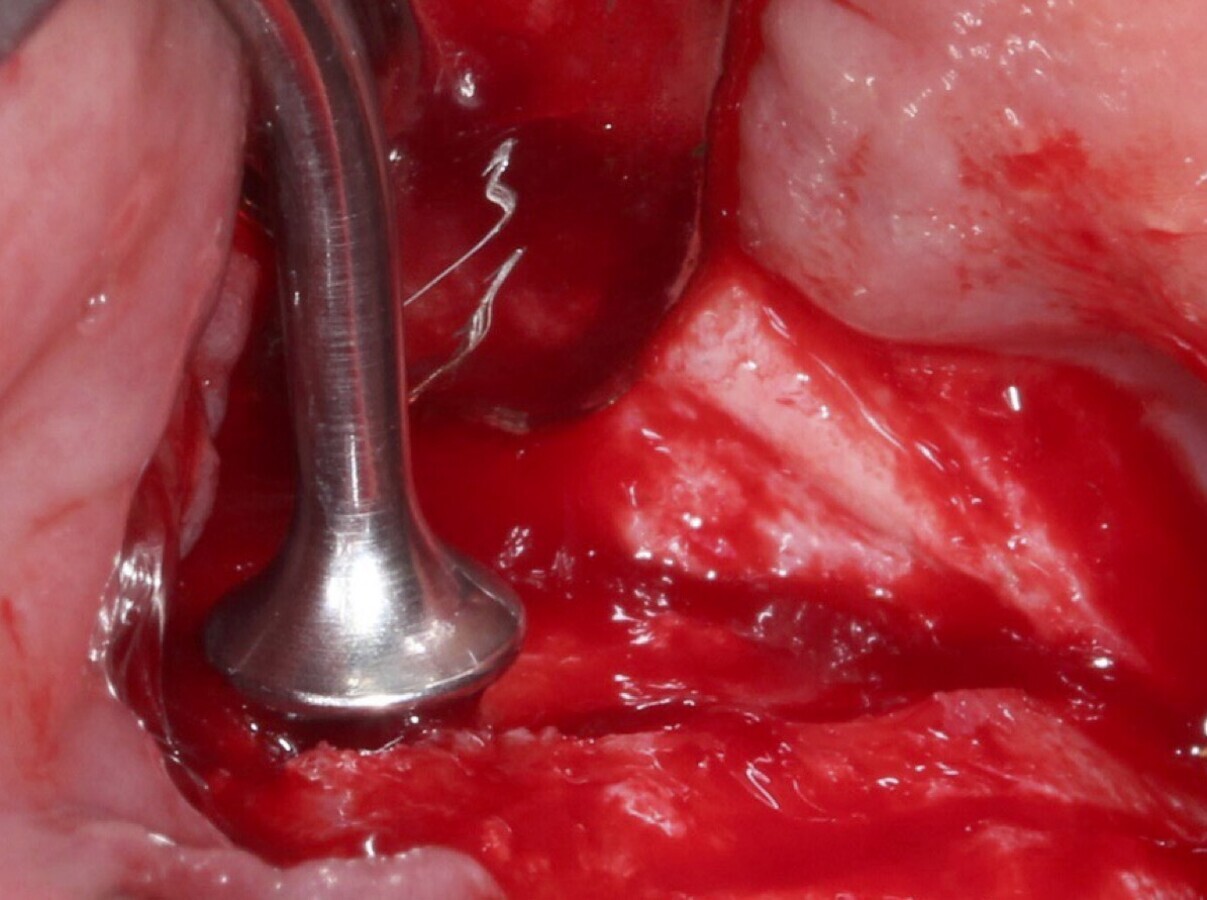

Figura 6. Técnica por retiro de la tabla ósea. Una vez retirada o fracturada la tabla ósea, se introduce el inserto de presión hidráulica entre la membrana de Schneider y los bordes de la ventana, con suaves movimientos se inicia el desprendimiento gracias al chorro de agua expulsado a través del inserto (Figura 7).

Figura 7. Inserto de presión hidráulica iniciando el desprendimiento de la membrana de Schneider (a, b ).

Figura 17. Inicio del desprendimiento de la membrana de Schneider con el inserto de presión hidráulica.